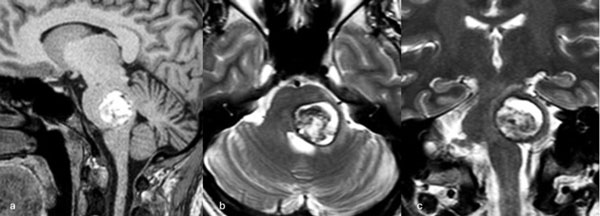

Caso 1: cavernoma mesencefálico

Una mujer de 35 años debutó con un cuadro de cefalea asociada a diplopía por parálisis del tercer par craneal izquierdo y hemihipoestesia del hemicuerpo derecho. La RM de encéfalo evidenció una malformación cavernomatosa tegmental izquierda con signos de sangrado reciente. Un año después del sangrado, la paciente fue sometida a una exéresis de la lesión mediante un abordaje suboccipital lateral y supracerebeloso infratentorial izquierdo (Figura 1), logrando una exéresis completa de la malformación (Figura 2). Después del procedimiento, la paciente no presentó nuevos déficits agregados.

Figura 1. Imágenes intraoperatorias bajo microscopía. Craneotomía suboccipital lateral. Se ingresa al mesencéfalo desde posterior por una ruta supracerebelosa infratentorial lateral. A y B) Corticotomía en surco mesencéfalo lateral. C) Identificación y resección en bloque de la malformación cavernomatosa. D) Revisión del lecho, sin remanente.